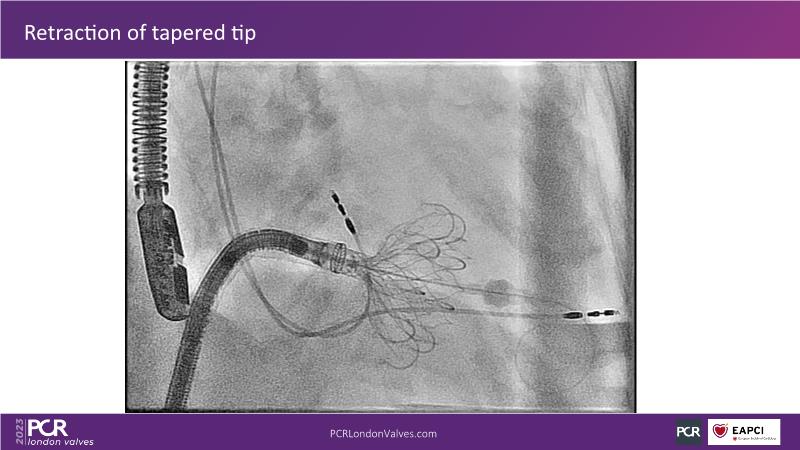

This session explores the features of the PASCAL Precision and the EVOQUE tricuspid replacement systems through simulators and case presentations, while a panel of experts discuss the technology, witnessing live demonstrations of treating mitral and tricuspid regurgitation patients.

- To learn about the differentiating features of the PASCAL Precision system showcased in a series of simulators alongside case presentations

- To interact with a panel of experts discussing the PASCAL Precision system technology and showcasing, live, its different key features in action and how they help treat mitral regurgitation and tricuspid regurgitation patients

- To introduce the EVOQUE tricuspid replacement system showcased with a simulator and a case presentation